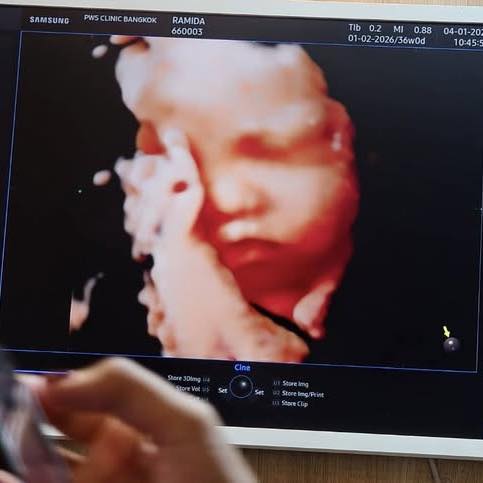

ลูกสาวตัวน้อยกำลังจะลืมตาดูโลก ห้องน้อยๆ ถูกจัดเตรียมด้วยความรัก เตียง เสื้อผ้า ของใช้ทุกชิ้น เต็มไปด้วยความหวังของพ่อแม่ คลิปเมื่อวันที่ 8 ม.ค. 69 คือภาพของหัวใจที่เชื่อว่า

ลูกสาวตัวน้อยกำลังจะลืมตาดูโลก ห้องน้อยๆ ถูกจัดเตรียมด้วยความรัก เตียง เสื้อผ้า ของใช้ทุกชิ้น เต็มไปด้วยความหวังของพ่อแม่ คลิปเมื่อวันที่ 8 ม.ค. 69 คือภาพของหัวใจที่เชื่อว่า “อีกไม่นาน…เราจะได้กอดกันจริงๆ”